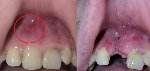

image.png

В каком возрасте нужно начинать исправлять зубы? Когда все молочные выпадут? В пуберат?

>>1635836

Смотря что. Если какие-то проблемы с челюстями, то надо фиксить лет до 14, когда можно пофиксить без хирургии. Аномалии прикуса можно предупредить в раннем детстве, например, отучив ребенка сосать палец. Если какие-то молочные проебались не вовремя, то ща вроде врачи как-то могут это исправить. Брекеты обычно любят на загнивающем ставить в подростковом возрасте, когда зубы уже полностью сменились, чтобы к первому курсу уже с ровными зубами ходить.